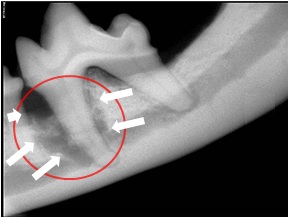

At Dunedin Animal Medical Center Dental X-Rays are included every-time your pets' teeth are cleaned. Unlike humans that can say "Doc it hurts over here" our pets can not verbalize their pain.  It is up to their Pet Parents and Veterinarians to locate any discomfort and correct it.  Most Dental Disease occurs below the gumline and Dental X-rays are essential in its diagnosis.

The bone-loss (white arrows) on these Dental X-rays may never have been found if Dental X-Rays had not been taken.